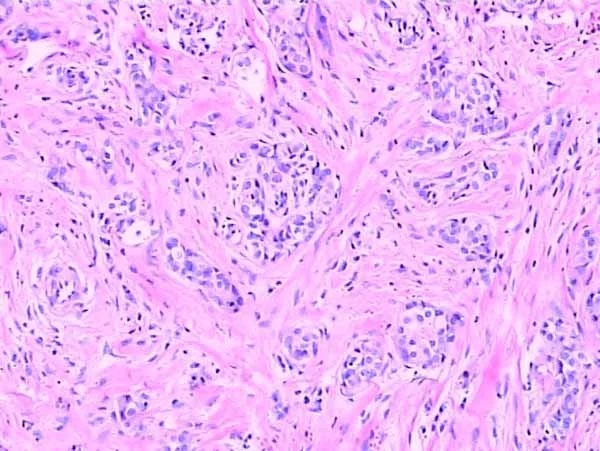

染色的目的是使细胞组织内的不同结构呈现不同的颜色以便于观察。未经染色的细胞组织其折光率相似,不易辨认。经染色可显示细胞内不同的细胞器及内含物以及不同类型的细胞组织。染色剂种类繁多,应根据观察要求及研究内容采用不同的染色剂及染色方法,还要注意选用适宜的固定剂才能取得满意的结果。经典的苏木精(Hematoxylin)和伊红(曙红,Eosin)染色法是组织学标本及病理切片标本的常规染色,简称HE染色。经HE染色后,细胞核被苏木精染成紫蓝色,多数细胞质及非细胞成分被伊红染成粉红色。由于苏木精是带阳离子的染料,染液呈碱性,核内染色质及胞质内核糖体等物质对这种染料有亲和性,称嗜碱性;而带阴离子的染料伊红配制的染液呈酸性,对这种染料的亲和性,称嗜酸性。有时不同的组织结构还需要用特殊的染料及染色方法加以显示,称特殊染色。有些细胞组织经硝酸银浸润后,可使溶液中银离子还原成金属银或银粒附着在细胞组织上,呈棕黑色,这种性质称亲银性,而有些细胞组织本身不能使硝酸银的银离子还原成金属银,还需加还原剂才能将银离子还原,称嗜银性。